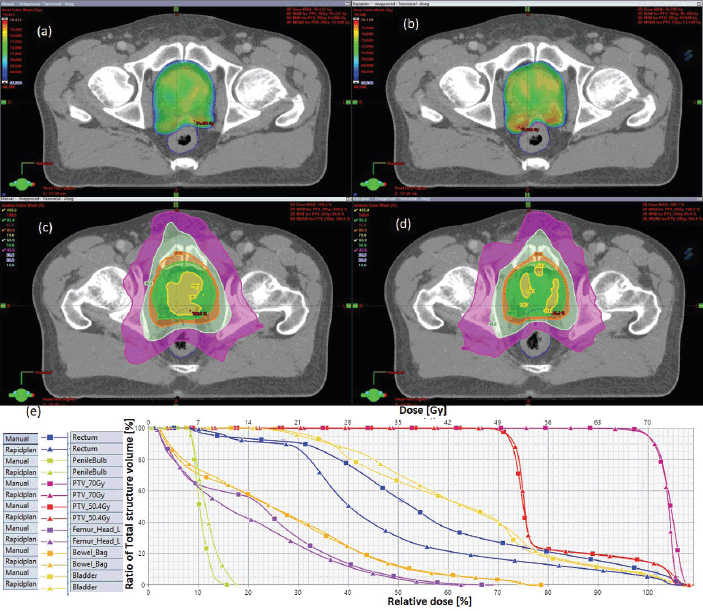

Figure 1. Typical two-dose level prostate SIB plan comparing: (a) 95% PTV70 for VMP, (b) PTV70 for VAP, (c) colour wash – PTV50.4 for VMP, (d) colour wash – PTV50.4 for VAP and (e) DVH for VMP versus VAP showing the two PTVs and OARs.

- The prostate plans: Both the VAP and VMP methods achieved the rectum V50Gy ≤ 50% constraint; however, VAPs calculate lower doses than the corresponding VMPs (16.5 versus 30.6: p = 0.01).

Table 2 indicates that, on average, the dose constraints for head and neck OARs like optic chiasm, eye lens, brain stem and spinal cord were adequately achieved by both methods, as explicitly reflected in Figure 3a. The same was true for prostate cases, where all pelvic OARs are within limits, apart from the bowel bag. Furthermore, although both methods achieved the rectum: V50Gy ≤ 50% constraint, VAPs predicted much lower doses than the corresponding VMPs (Dmean of 16.5 Gy versus 30.6 Gy and p = 0.01). This implies that the auto-plans provide better sparing of the rectum, which means that the training plans that were used to build the Rapidplan® model pushed harder on the rectum than manual planners, giving a rectal protective measure. This inclination is well reflected in Figure 1 (c, d, and e) showing the dose distribution for VAPs, VMPs and DVH curves. For patients with oesophageal cancers, VAPs showed better OAR sparing than VMPs as reflected in Table 2 and Figure 3b and c, which compares VAPs and VMPs planned dose and volume limits for oesophagus OARs. The results in Table 2 further show that for both cervical and rectum plans, and for both planning methods, failed to achieve the bladder dose constraint. This is attributed to the fact that most of our patients presented with advanced cancer exhibiting extensive pelvic nodes, resulting in a large bladder volume within the PTV. Both the cervical and rectum plans had the highest average PTVs of 1,452 ± 374 and 1,602 ± 153 cm3, compared to 803 ± 191, 372 ± 95, 1,077 ± 280 and 1,078 ± 280, for head and neck, oesophagus, breast and prostate, respectively. A general observation from the box-and-whisker plots is that manual plans have larger standard deviations than auto plans, which reaffirms that auto-planning generates more consistent plan quality, while manual plans are dependent on the planner’s experience.